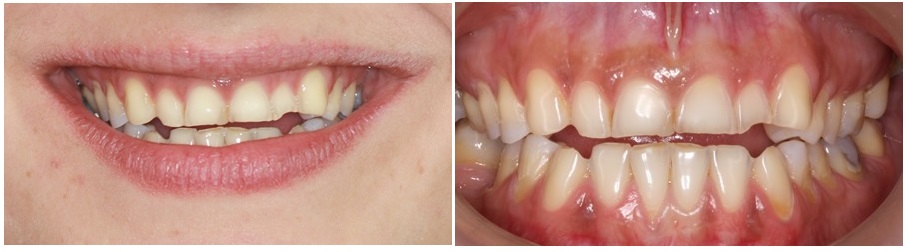

Following you see a case I treated 15 years ago, with porcelain crowns, covering the entire tooth surface of each tooth.

Preparing eroded teeth for crowns is a useful practice, but quite aggressive on teeth that already suffer substantial deterioration due to erosion.

Following is a case of one patient, that suffered significant loss of tooth substance from erosion and was treated with this contemporary protocol.

The patient was unhappy with her smile, and she also had difficulty chewing as the teeth were reacting to all thermal stimuli, hot or cold.

The main reason that made her seek dental care, was smile esthetics. Her teeth appeared small and had rough incisal edges, that were fracturing often, exacerbating the problem day after day.

Most teeth had lost their enamel and a significant portion of dentin. Teeth had also lost their anatomical features while the height of the lower third of her face had decreased.